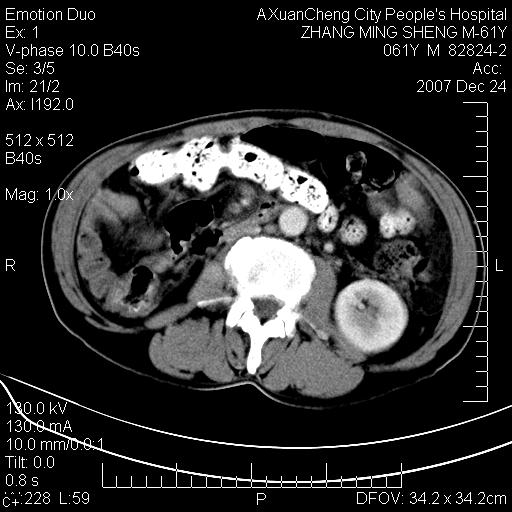

标题: CT11031:M61Y,胰腺占位

大家侃侃门静脉和胆管系统怎么回事,肝内转移?

胰腺癌肝转移

2,肝内多发结节状低密度占位,伴门脉及肠系膜上v栓子形成.考虑a;门脉及肠系膜上v血栓后肝改变.b;弥漫型肝癌伴门脉及肠系膜癌栓.

肝硬化,门脉高压,脾肿大;弥漫性肝癌,肝内、门脉、腹膜后淋巴结转移,肝内外胆管扩张,胰头区占位,建议mr检查

胰腺癌伴肝内转移;门脉、肠系膜上v癌栓形成。

考虑为:胰腺癌伴肝脏转移、腹膜后淋巴结转移,门静脉及肠系膜上静脉瘤栓形成。

胰体尾癌伴肝内转移,门静脉及肠系膜上静脉瘤栓形成.